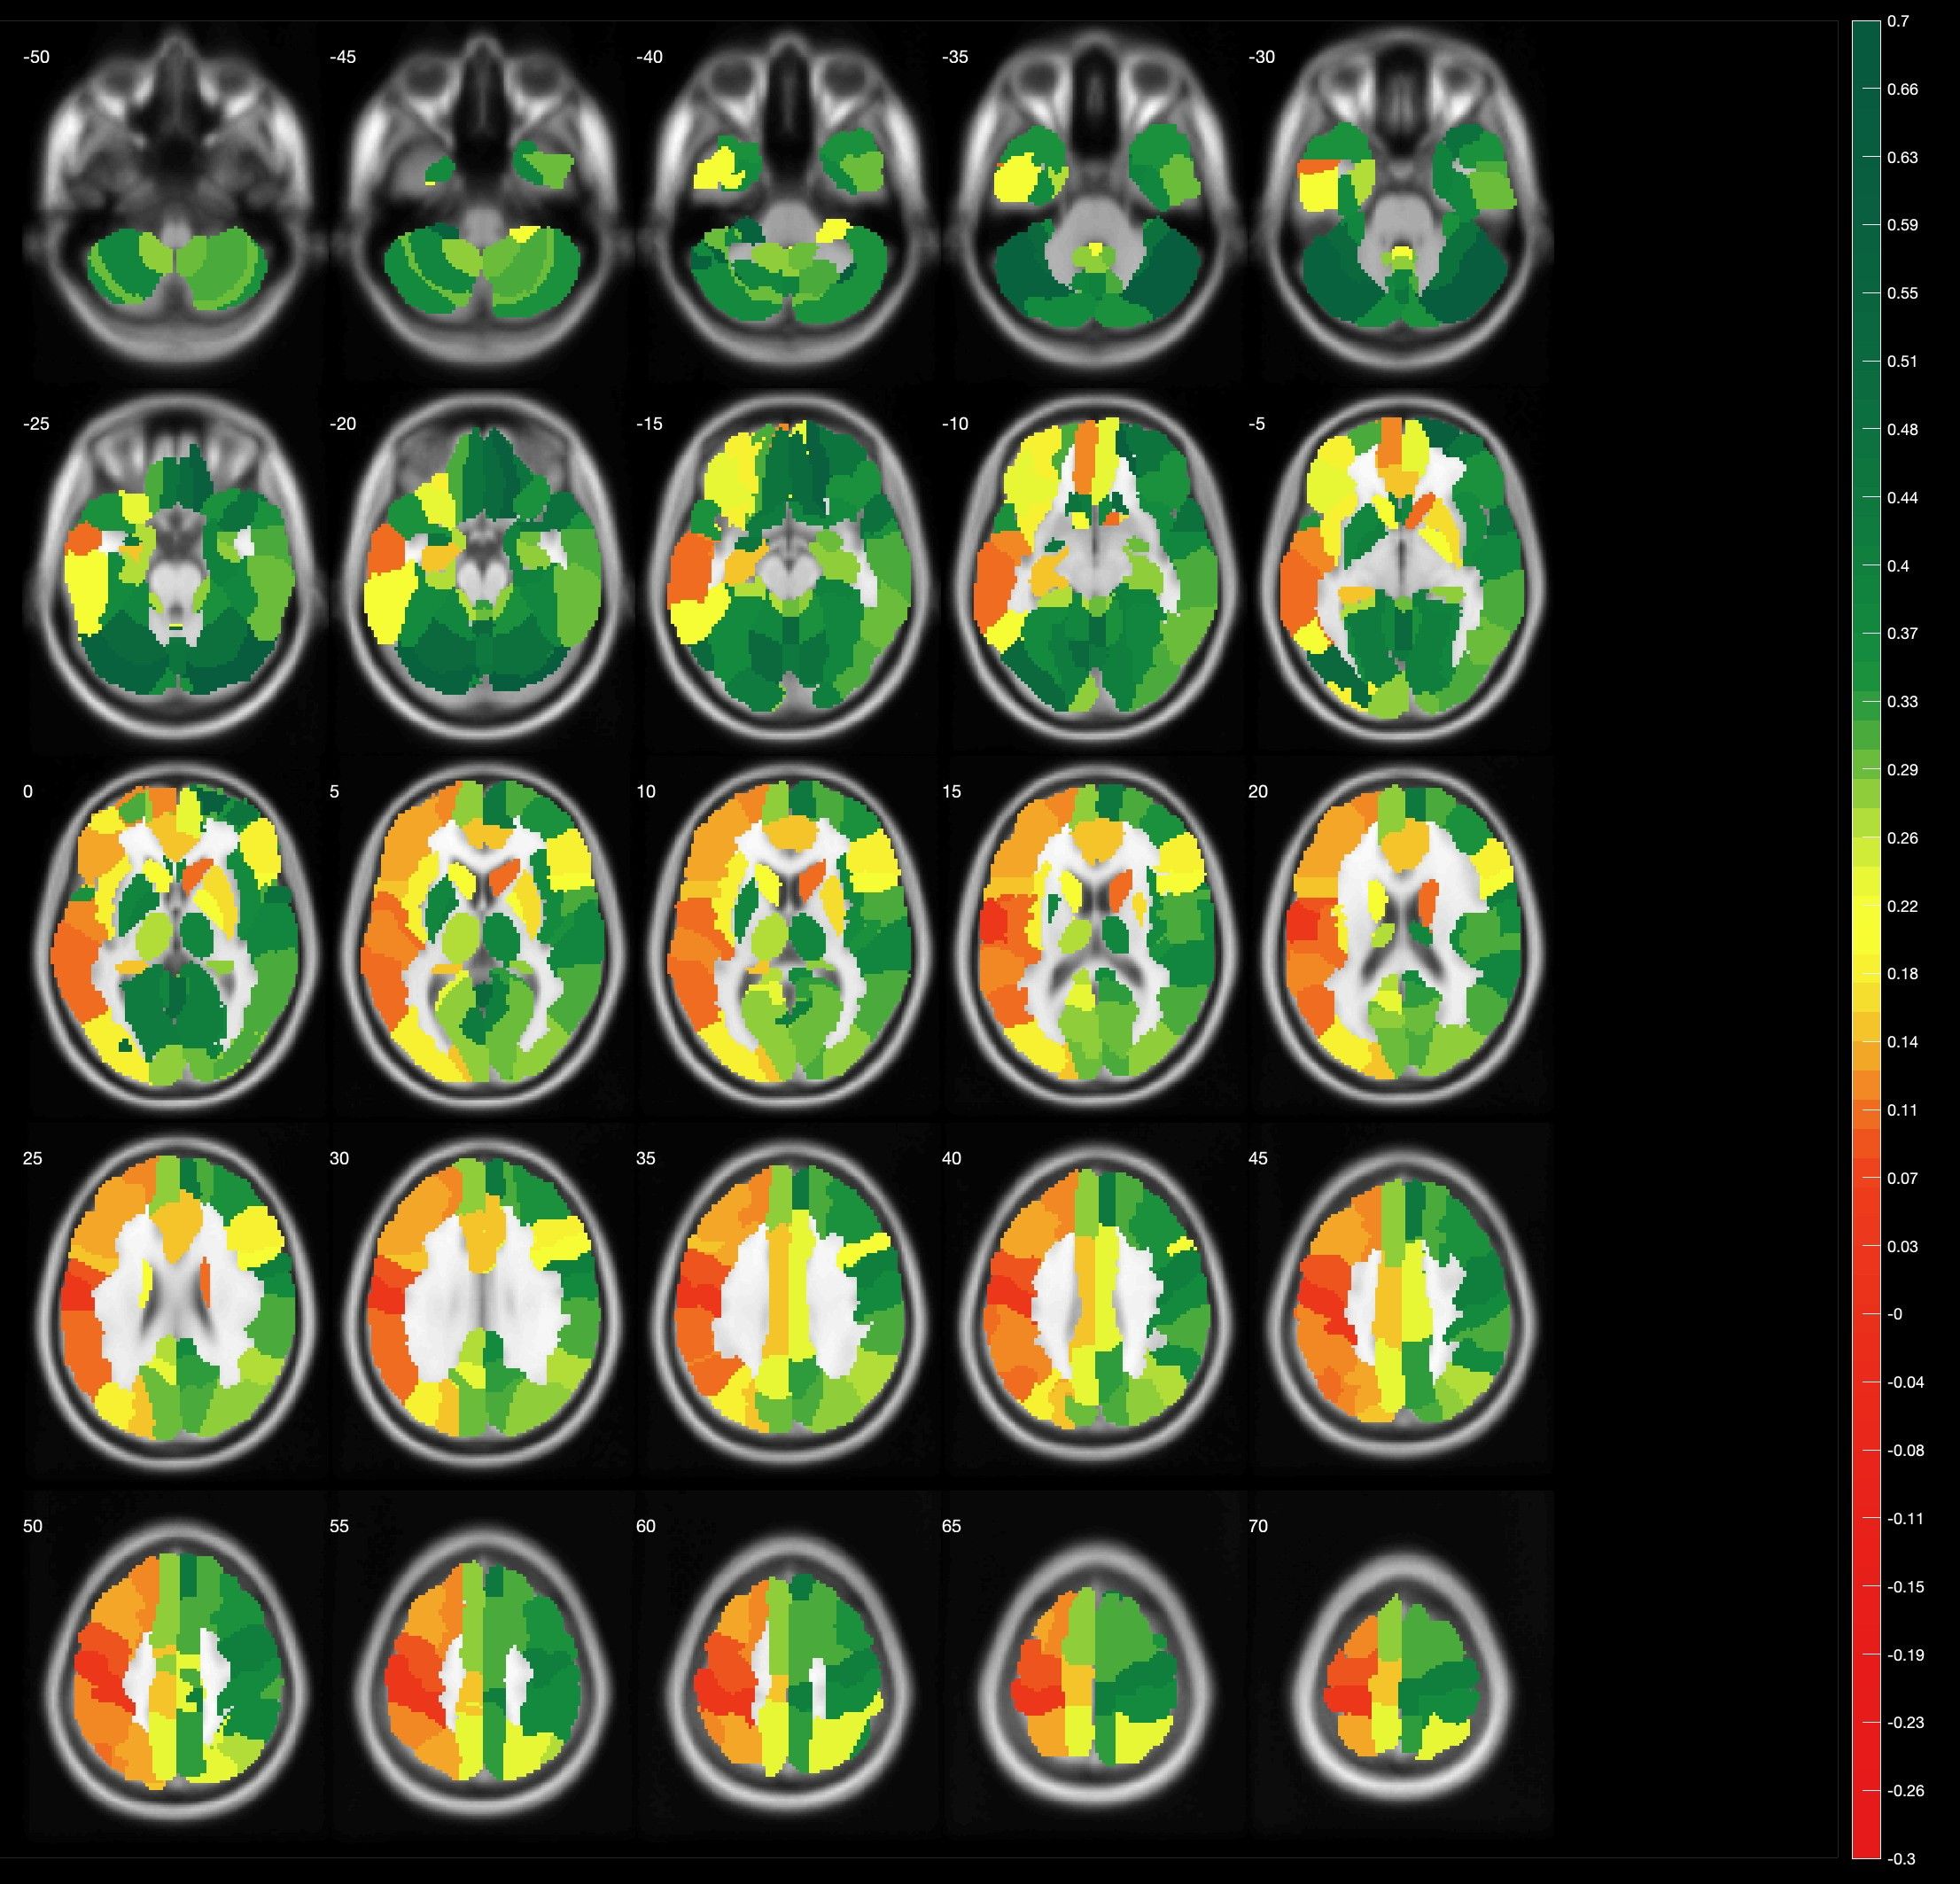

In der konventionellen Angiographie und im konventionellen MRT können selektiv die Gefäße, der Blutfluss, und Gewebe gut dargestellt werden. Diese Untersuchungen erbringen jedoch keine Aussage über den absoluten Blutfluss im Gehirn. Adaptierte Untersuchungen des MRTs, sowie auch des CTs zur Messung der Hirndurchblutung (Perfusion) haben sich in der Vergangenheit bei Moyamoya Patienten auf Grund der Kollateralen als zu wenig sensitiv gezeigt, um die Durchblutung zuverlässig darzustellen. Durch die eigene Erforschung des funktionellen MRTs haben wir eine Untersuchung etabliert, welche die Reaktivität der Hirngefäße (und somit indirekt die cerebrale Durchblutungsreserve) darstellen kann. Beim sogenannten "breathhold", also Atemanhalte-fMRT müssen die Patienten in mehreren Zyklen für jeweils wenige Sekunden die Luft anhalten. Dadurch erhöht sich die CO2 Konzentration im Blut und die Hirngefäße stellen sich weiter. Diese Veränderung des Blutflusses kann dann indirekt gemessen werden. Da es sich hierbei um eine sehr neue Methode handelt, ist zu erwähnen, dass medizinische Entscheidungen primär ausschließlich in Zusammenschau aller Befunde und bei jeglicher Unschlüssigkeit mit dem ergänzenden PET-CT getroffen werden müssen. Das fMRT hat sich jedoch als exzellentes Screening-Tool für die langfristigen Nachkontrollen erwiesen.

Unsere Forschungsbemühungen beziehen sich hierbei auf den Vergleich und die Weiterentwicklung des fMRTs in Korrelation zum PET/CT, die Reproduzierbarkeit des fMRTs, sowie die Kombination anderer MRT Sequenzen mit dem fMRT.

Darstellung im breathhold fMRT

Anatomische Darstellung der Hirndurchblutung gemessen im breathhold fMRT. Grüne Farbe zeigt eine regelhafte Durchblutung an, während die rötlicheren Farben eine unzureichende Hirndurchblutung anzeigen. Auffällig hierbei die Durchblutung im mittlere Hirnareal rechts (hellgrüne Kurve) im Vergleich zu allen anderen Hirnarealen und dem Kleinhirn (Cerebellum – gelbe Kurve), welches als Referenz dient.